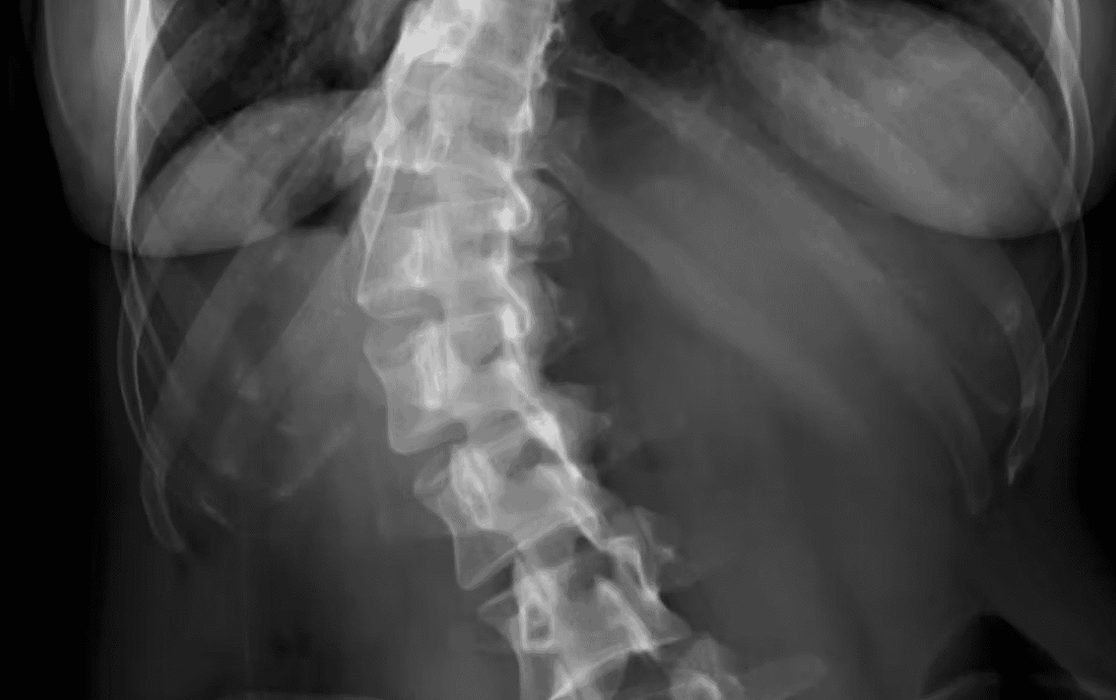

WHAT IS SCOLIOSIS?

Scoliosis is a curvature or deformity of the spine seen when looking from behind, where the spine should be straight, it curves.

Sometimes this curvature is obvious. Other times it’s subtle and goes unnoticed.

Tragically, scoliosis is rarely obvious at its onset, at the very stage when it may still be corrected.